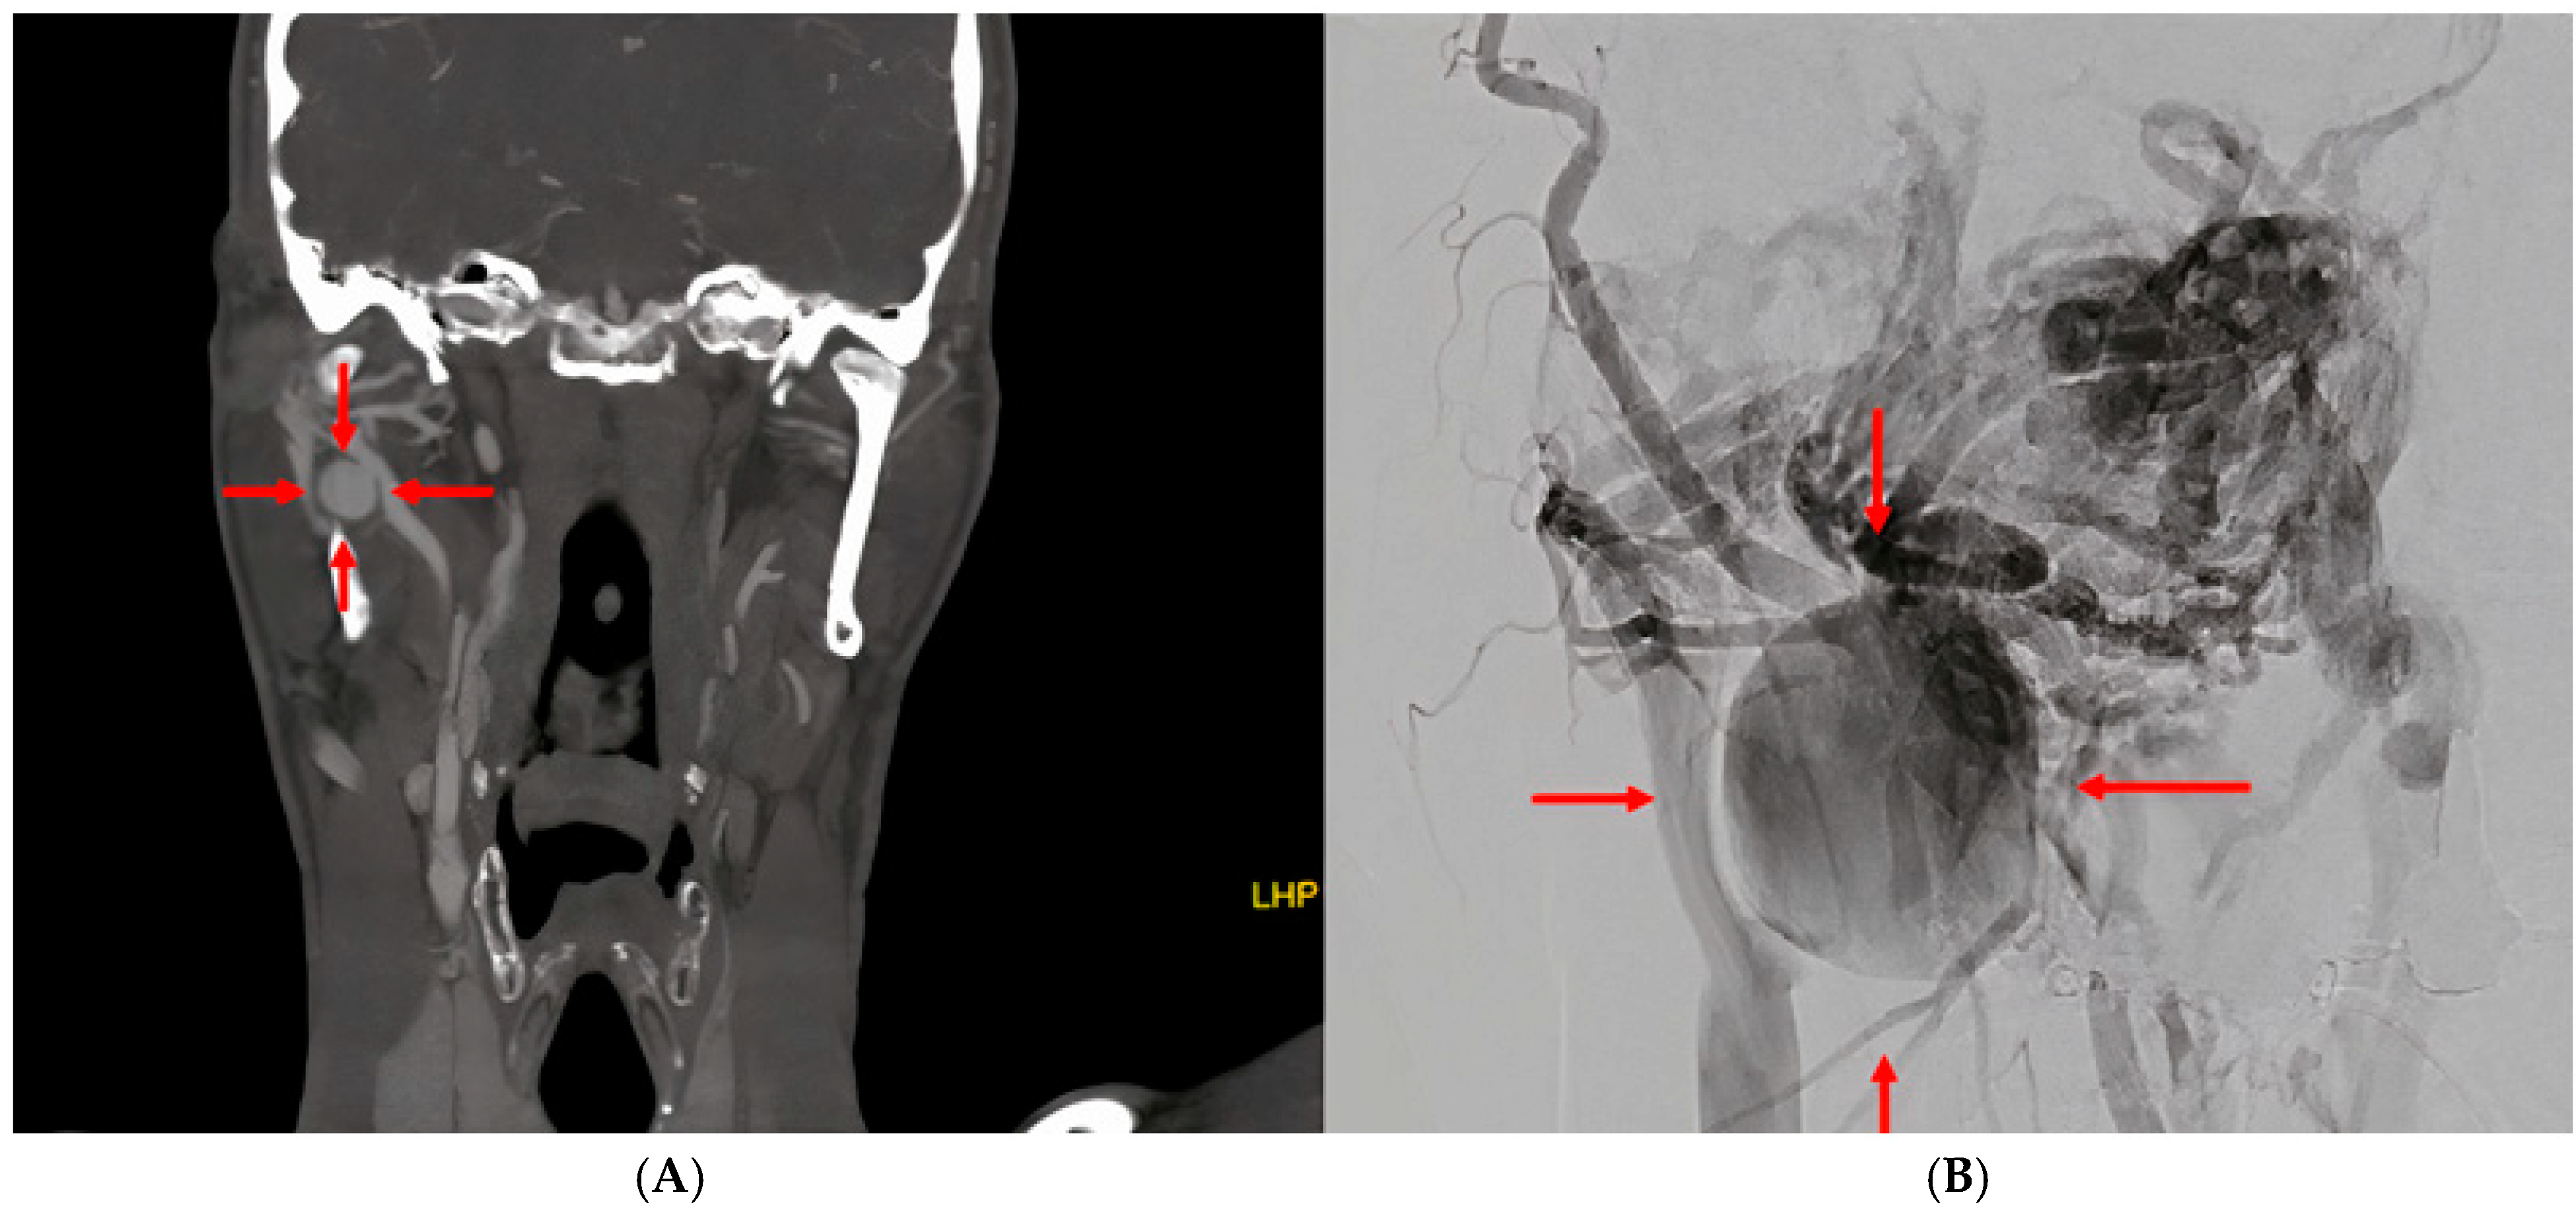

Arteriovenous Fistula with Pseudoaneurysm and Facial Palsy Following Bilateral Sagittal Split Osteotomy: A Case Report

2. Case Report